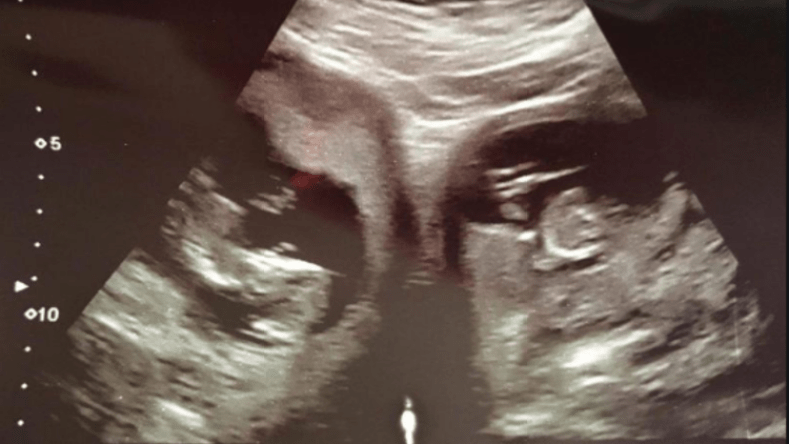

وضعت امرأة بريطانية حملها المتمثل في 3 توائم من رحمين منفصلين، وقال الأطباء إن مثل هذه الحالة نادرة تحدث مرة كل 25 مليون حمل.

وقالت وسائل إعلام بريطانية أن ميلانيا باسيت (32 عاما) من مقاطعة هامبشاير جنوبي بريطانيا، أنجت 3 توائم، توأم إناث كان في الرحم الأول، وذكر ثالث كان في الرحم الثاني، ما تم اعتباره حالة نادرة للغاية.

ولم تكن رحلة الحمل سهلة عليها، فالأمر كان صعبا ومختلفا، أما شكل الرحم في صور الأشعة فكان مختلفا عن بقية الأرحام، إذ كان شكله قريبا من القلب المقسوم إلى شطرين.

يذكر أن احتمال الحمل بتوائم في رحمين منفصلين أمر نادر للغاية ولا يزيد عن واحد في المليون، ويعتقد أن هناك عددا محدودا من الحالات التي تفضي إلى الحمل بثلاثة توائم، وحالة ميلانيا هي الأولى من نوعها في بريطانيا.